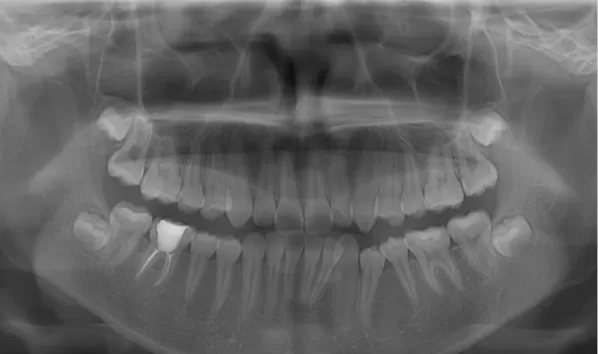

X-rays before treatment

[Panoramic Radiography/Lateral Cephalogram]